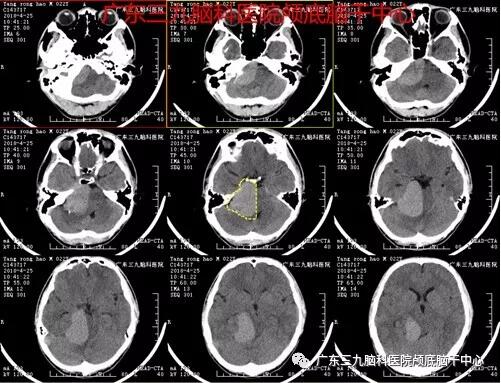

▲图1:右侧桥小脑角区及环池占位性病变,呈稍高密度影,病变内未见明确异常血管影

▲图2:术前DWI显示巨大囊性病变,考虑不典型胆脂瘤可能